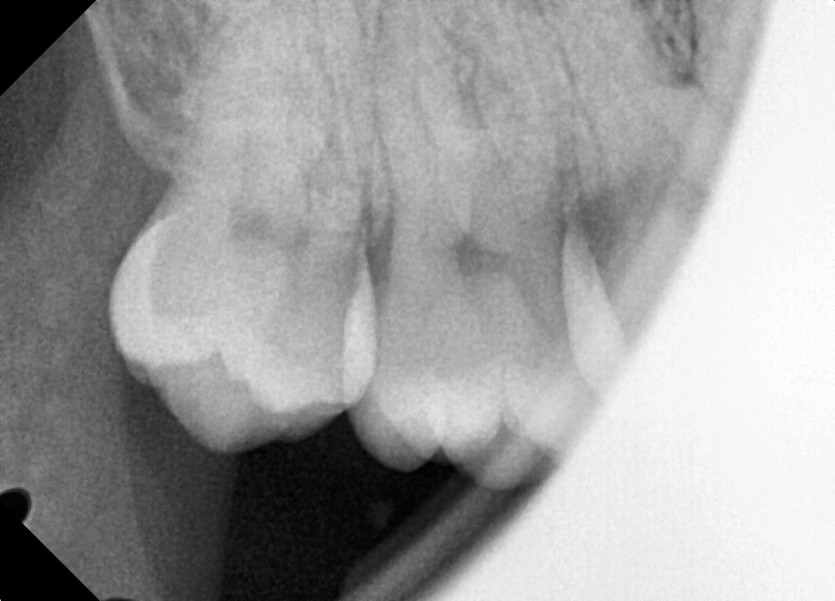

#18,28,48 사랑니 발치

구강 외과 전문의가 당일 발치했습니다.